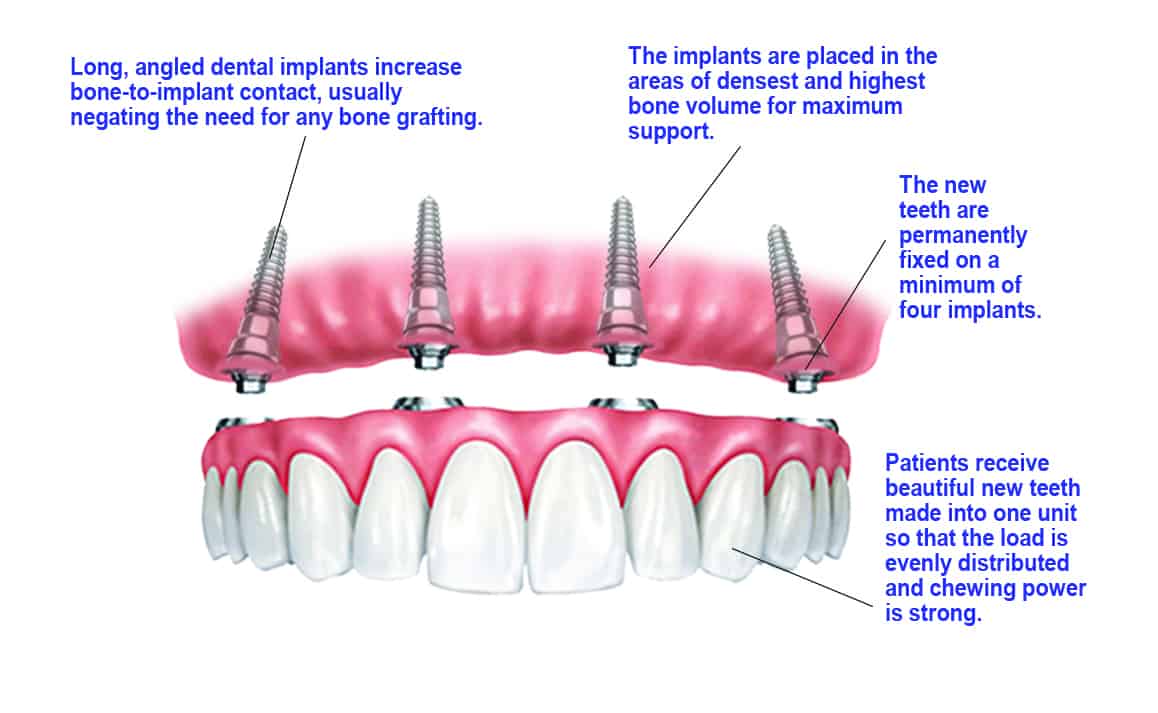

Using the All-on-4 procedure, Dr. Bhave will place four specially designed implants in strategic positions on the dental arch that contain the greatest bone volume and density. This ensures the best support of your implants. She places the rear implants at a forward angle so that they access the dense bone in the front of the jaw.

This technique eliminates the need for bone grafting for most patients, even those who have experienced severe bone loss are were previously told they were not eligible for implant treatment. All-on-4 is an efficient and affordable solution for getting permanently fixed-in teeth.